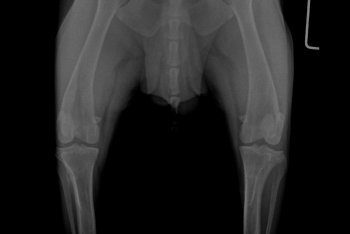

Garret Posted March 14, 2019 Share Posted March 14, 2019 Hi Guys, My dog has been diagnosed with IVDD since February 2nd of 2019. Im at a lost to treat him, please help. So far Im taking him for acupuncture 2x a week. He is being medicated with Analsik 2x a day, and I apply Glucosamine Gel over his joints. Since he has a hard time walking I'm trying to learn to express bladder him, but pooping is still something I can't figure out how to help him does it. So far my vet has diagnosed him with IVDD from looking at his Xray. But there is something that me and my doctor are not sure about which is the Xray on his neck, regarding what is near the AXIS of his neck. I don't know where to ask to next.. I have consulted with 5 vets and not one of them seems to be able to give a definite answer. Some say its a piece of the fracture that broke off, other speculate that it might be cancer. I'm really scared for my dog, and if anyone could help tell me more on what exactly is happening to my dog's neck. or at least point me where I could better ask these questions would help a lot! Link to comment Share on other sites More sharing options...